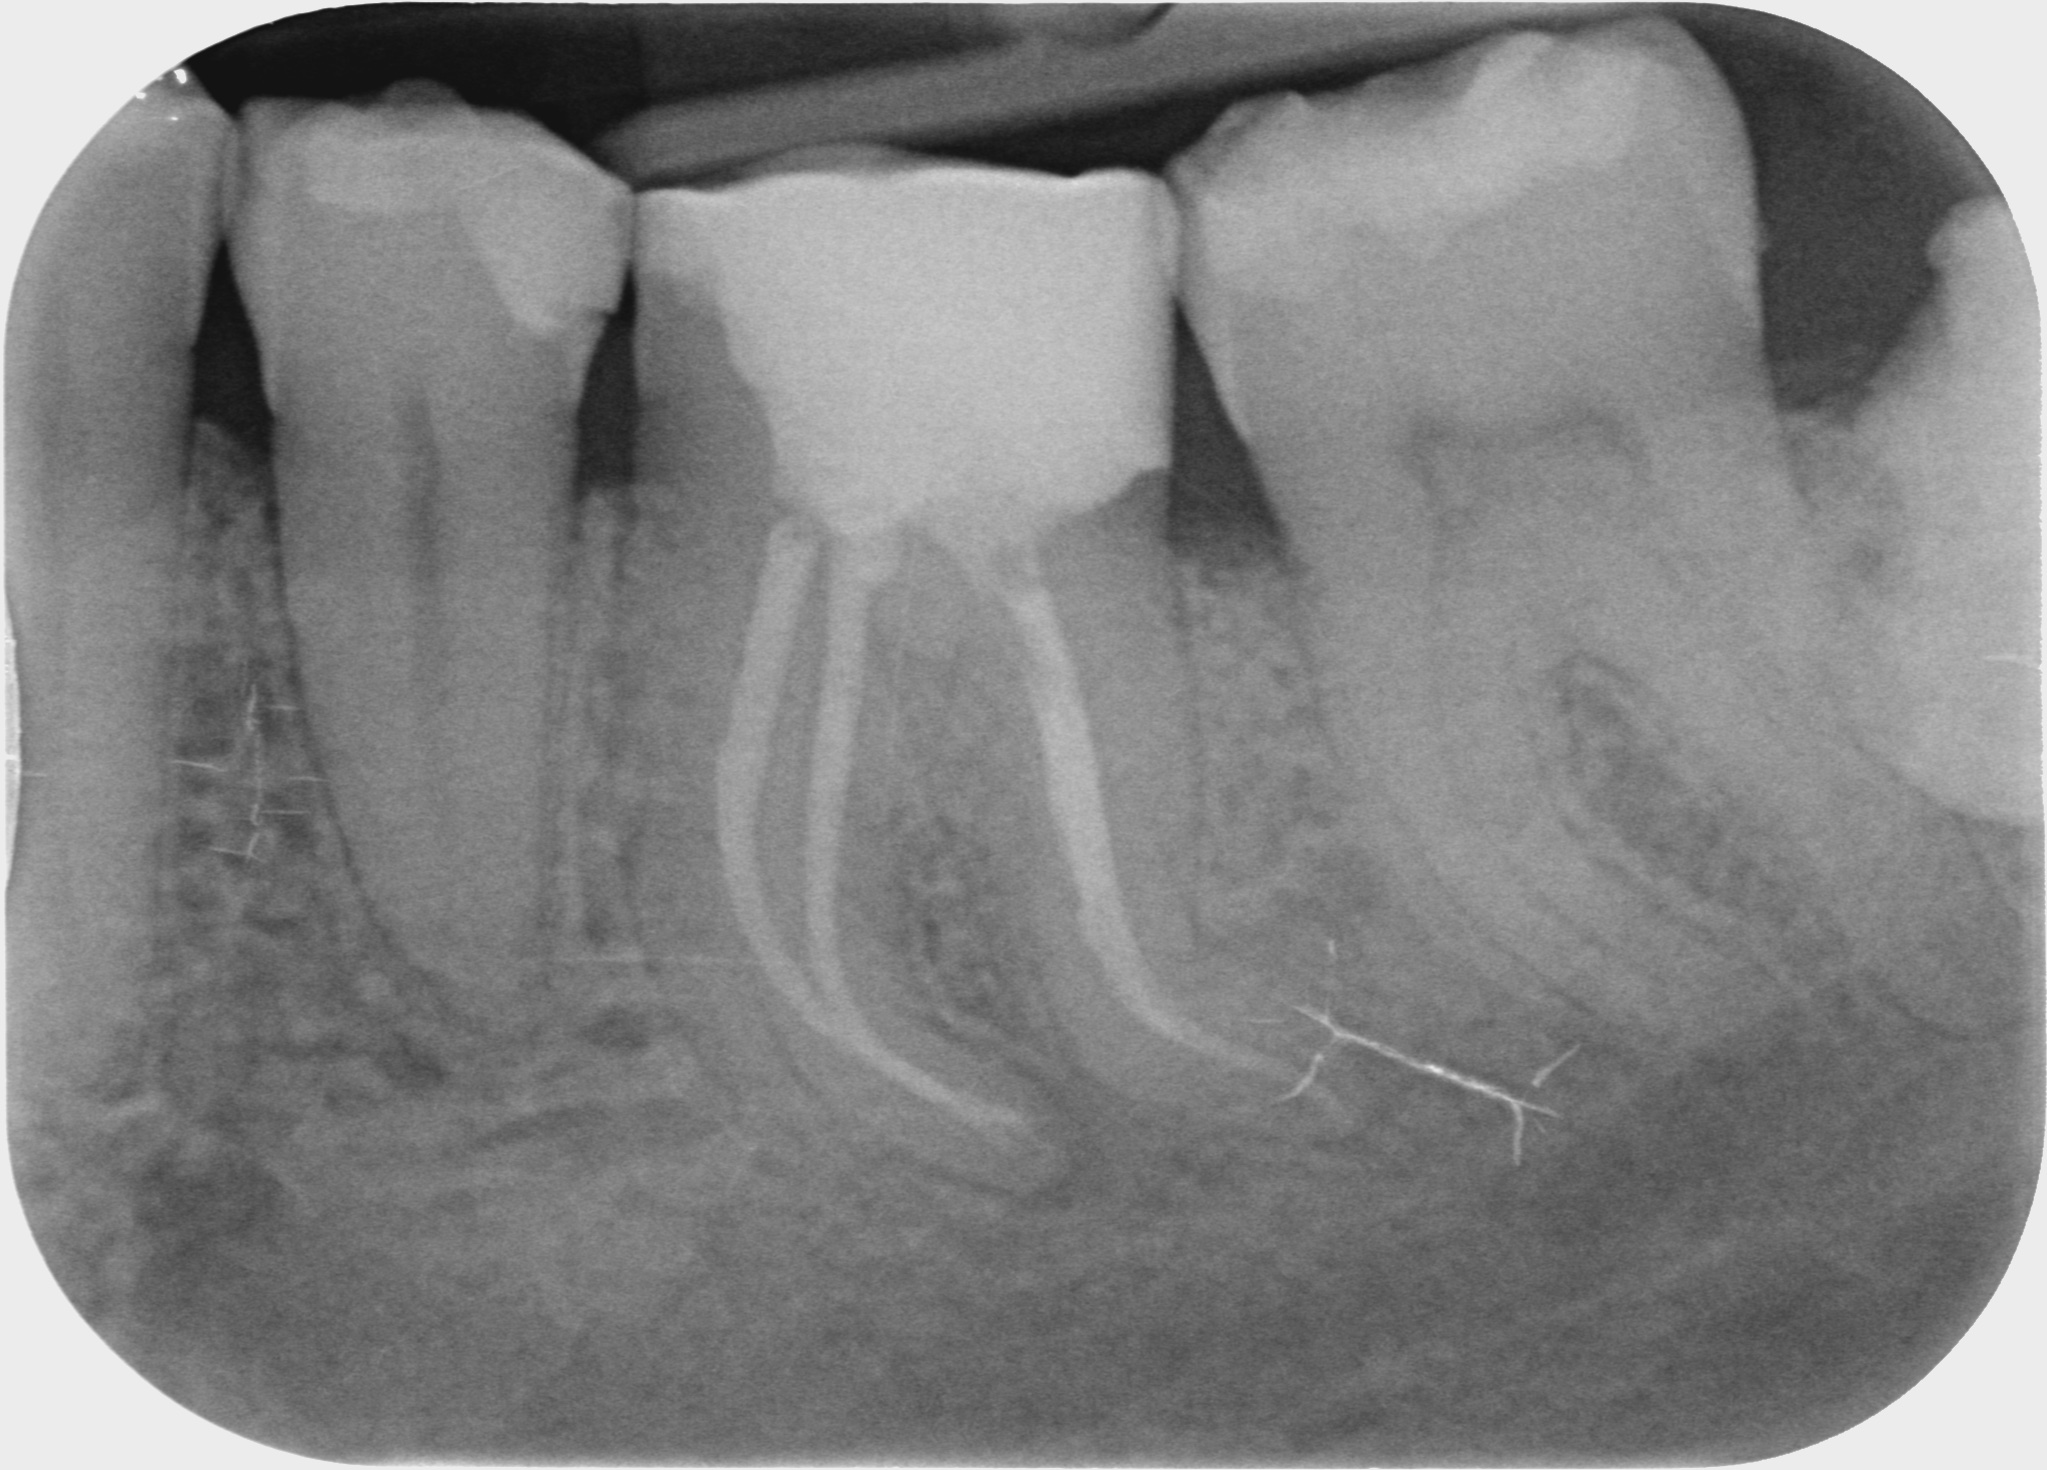

Bei einer Wurzelbehandlung wird der erkrankte oder abgestorbene Zahnnerv entfernt. Die komplexen Wurzelkanalsysteme werden mit speziellen Feilen aufbereitet, gereinigt und gründlich desinfiziert. Anschliessend erfolgt eine bakteriendichte Füllung der Hohlräume im Wurzelbereich.

Fallbeispiele

Zum Vergrössern klicken